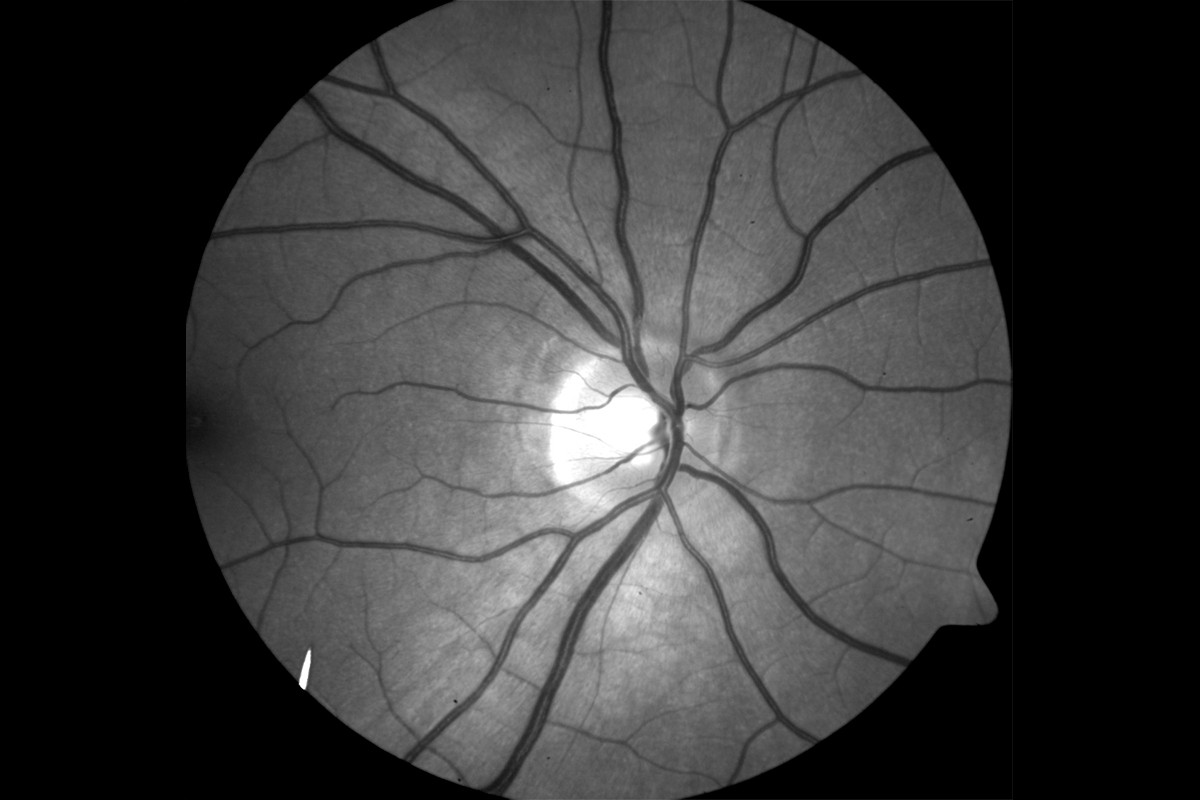

• VesselMap aric: Image of the ocular fundusVesselMap aric: Image of the ocular fundus

1. Images from the ocular fundus are taken by using an imaging system.